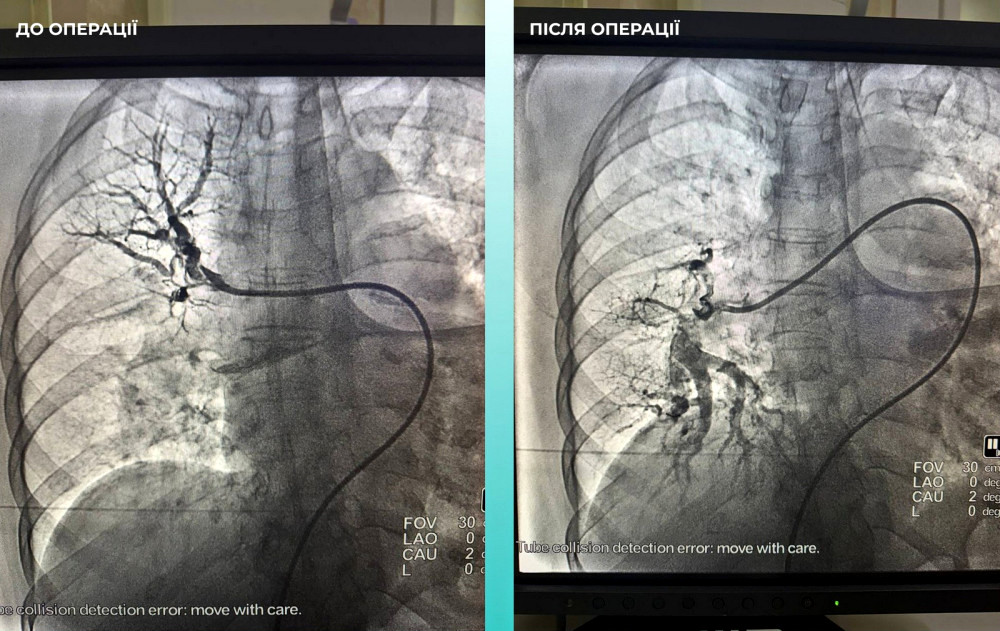

Мультидисциплінарна команда лікарів прийняла рішення про проведення одночасної тромбектомії як в мозковій, так і в легеневій артеріях.

Операція пройшла успішно. Наразі пацієнтка відчуває значне полегшення: вона в свідомості та вже може рухати кінцівками.